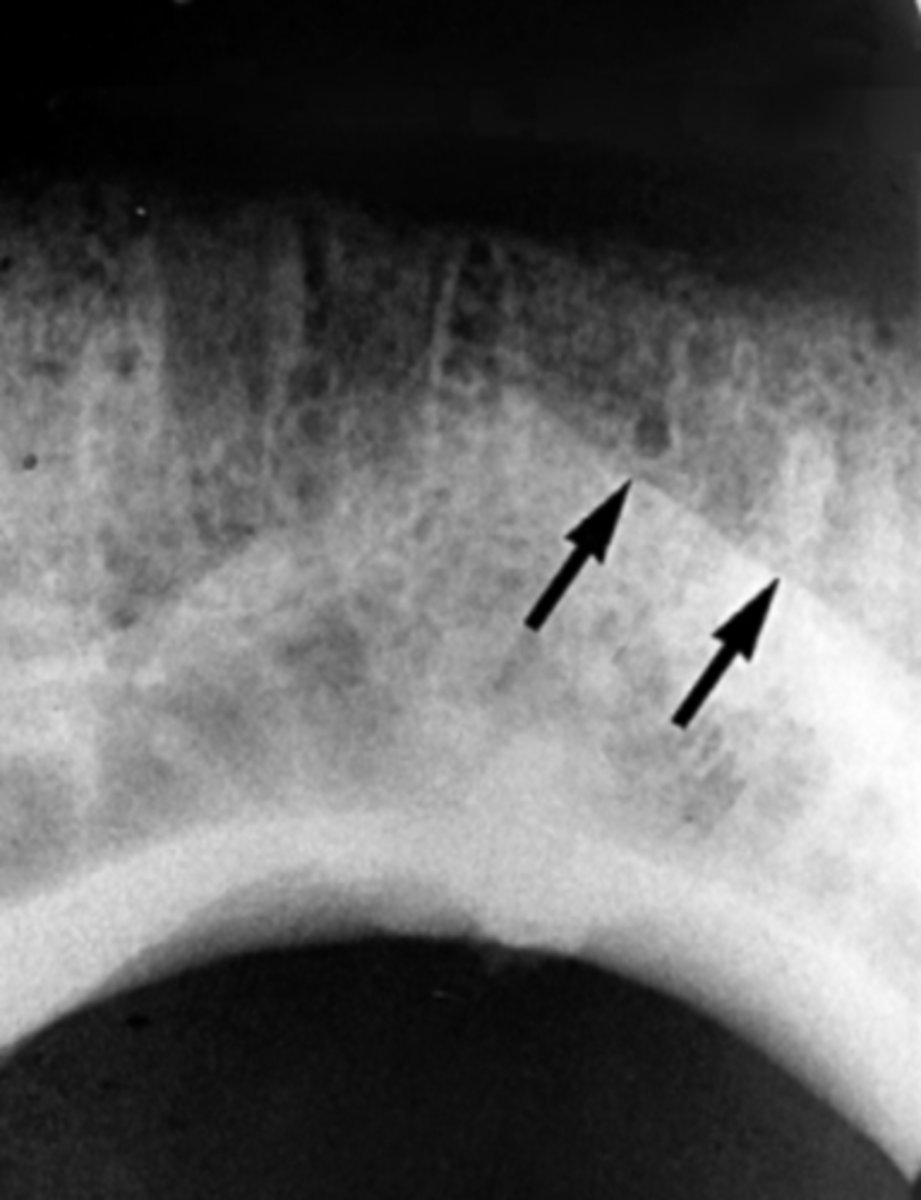

Nasopalatine (incisive) foramen

Identify the round, ovoid radiolucent structure indicated by the black arrows.

New cards

Nasopalatine canal

Superior foramina of the nasopalatine duct

Name the two round radiolucencies indicated.